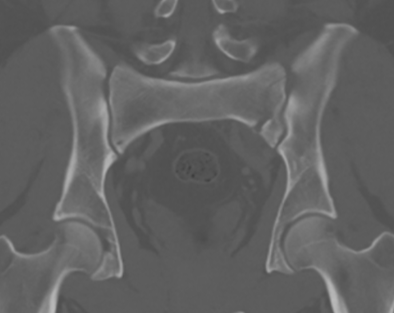

Zone 1 sacral fracture